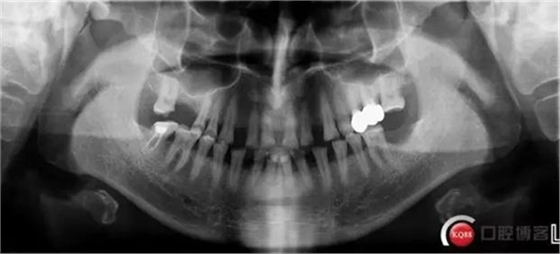

X線檢查:

CBCT檢查: